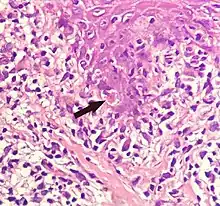

Civatte body

A Civatte body (named after the French dermatologist Achille Civatte, 1877–1956)[36] is a damaged basal keratinocyte that has undergone apoptosis, and consist largely of keratin intermediate filaments, and are almost invariably covered with immunoglobulins, mainly IgM.[37] Civatte bodies are characteristically found in skin lesions of various dermatoses, particularly lichen planus and discoid lupus erythematosus.[37] They may also be found in graft-versus-host disease, adverse drug reactions, inflammatory keratosis (such as lichenoid actinic keratosis and lichen planus-like keratosis), erythema multiforme, bullous pemphigoid, eczema, lichen planopilaris, febrile neutrophilic dermatosis, toxic epidermal necrolysis, herpes simplex and varicella zoster lesions, dermatitis herpetiformis, porphyria cutanea tarda, sarcoidosis, subcorneal pustular dermatosis, transient acantholytic dermatosis and epidermolytic hyperkeratosis.[37]